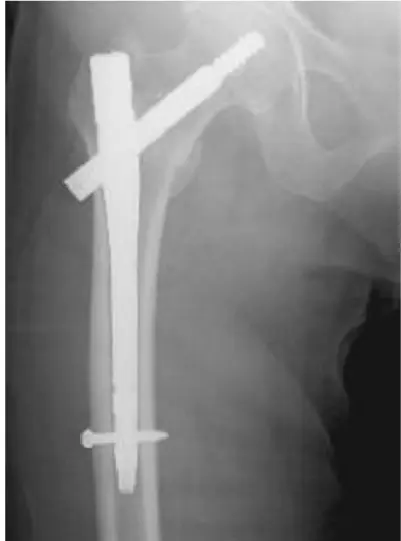

全国の病院では、大腿骨骨折の手術までに平均4〜5日かかるのが現状です。当院では原則48時間以内の手術を目標とし、万全の体制を整えています。大腿骨骨折は「治療の早さ」が回復を左右する重要な疾患だからこそ、これほど手厚く手術室を確保し、患者さんの一日も早い回復を支えます。